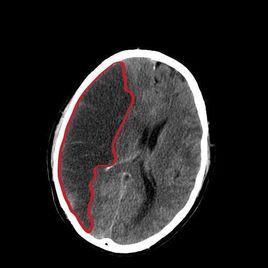

而多數腔隙性腦梗塞由於一般發病部位多,病灶面積小,所以又稱為多發腔隙性腦梗塞。腔隙性腦梗塞的臨床診斷一般是指直徑在15—20毫米以下的新鮮或陳舊性腦深部小梗塞的總稱。這些小動脈閉塞後,可引起多個大小不同的腦軟化灶,最後形成大大小小的腔隙,它可通過頭部CT確診。常見3—10毫米的低密度區,小於2毫米的病灶CT不能顯示。